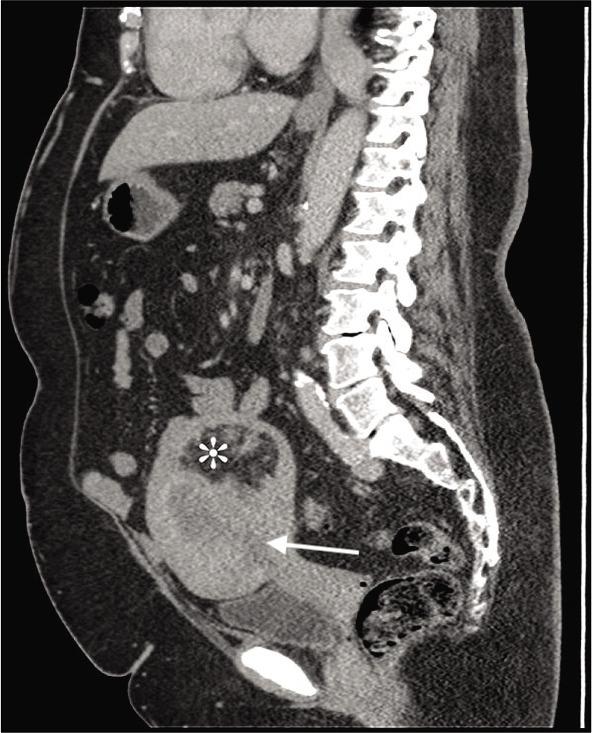

We describe a case of a 63-year-old woman referred to an oncologist for treatment of endometrial adenocarcinoma. A computed tomography scan revealed the incidental finding of a 11.5 × 10.5 × 9.0 cm myomatous mass in the uterine corpus adjacent to, yet uninvolved with, the adenocarcinoma. Histopathological analysis confirmed the mass to be a lipoleiomyoma, a rare single variant of lipoma. These fatty tumors present similar to leiomyomas and as such are generally not harmful; however, the potential exists for diagnostic confusion with other uterine tumors. This case serves to further illuminate the findings associated with these rare tumors.

我们描述了一例63岁女性因子宫内膜腺癌转诊至肿瘤学家处接受治疗的病例。计算机断层扫描偶然发现子宫体有一个11.5×10.5×9.0厘米的肌瘤样肿块,与腺癌相邻但未受其影响。组织病理学分析证实该肿块为脂肪平滑肌瘤,这是一种罕见的脂肪瘤单一变体。这些脂肪性肿瘤的表现与平滑肌瘤相似,因此通常无害;然而,与其他子宫肿瘤存在诊断混淆的可能性。本病例有助于进一步阐明与这些罕见肿瘤相关的发现。